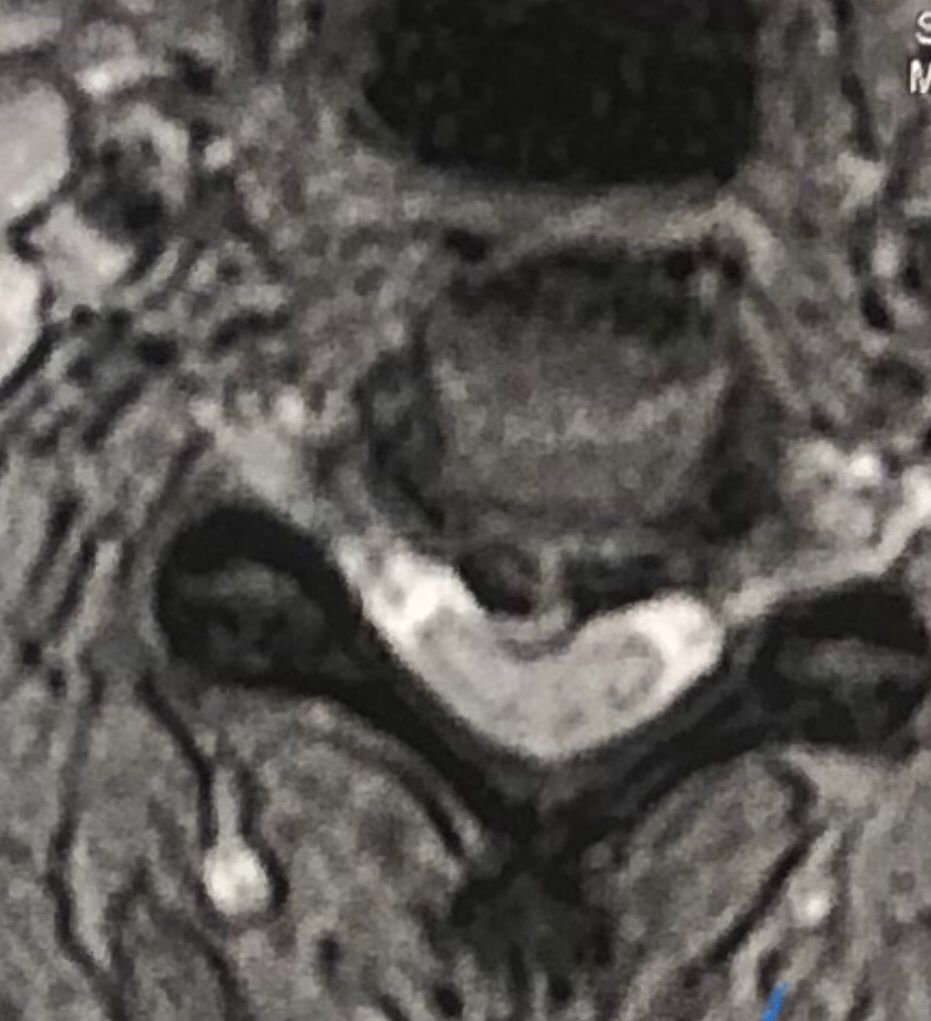

41 years old man presented to my clinic in October 2023 with acute and sever R neck pain with radicular pain to his R upper extremity along C6 dematom since 2 weeks ago. Examination didn’t show any upper motor signs. Was suggested urgent surgery

I ordered EMG/ NCV : showed mild R C6, C7 irritation without any active axonal loss

In his MRI was reported R. para R. IVF Massive extrusion. I decided to control his pain and manage this patient with reevaluation of patient every other session. For 5 sessions i just used acupuncture and laser and IFC and mild adjustments to his R. T3-T7 and mild arthosteem to above and below involved segment. Cervical adjustment considered contraindicated for this patient. From session 6th- 8th i started to use mild/gentle cervical decompression. He used soft cervical collar all the time. His pain decreased by 80 percent

I gave him cervical traction pump to be used 3-5 times per day at home for the next 3 months and i released the patient. He was evaluated every week once for one month and after that every 2 weeks. After 3 month I repeated MRI. Size of the herniated disc was reduced greater than 50 percent. Asked him to do another mri in 6 months

MRIs before and after proper management of this patient: